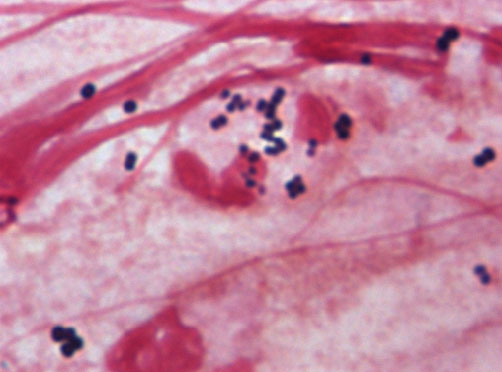

本学の医学科および工学資源学生、日赤看護大学の学生に、感染症学、渡航医学、感染制御学の講義を実施しています。このほか、グラム染色法の実習や、手指衛生の演習も行っています。